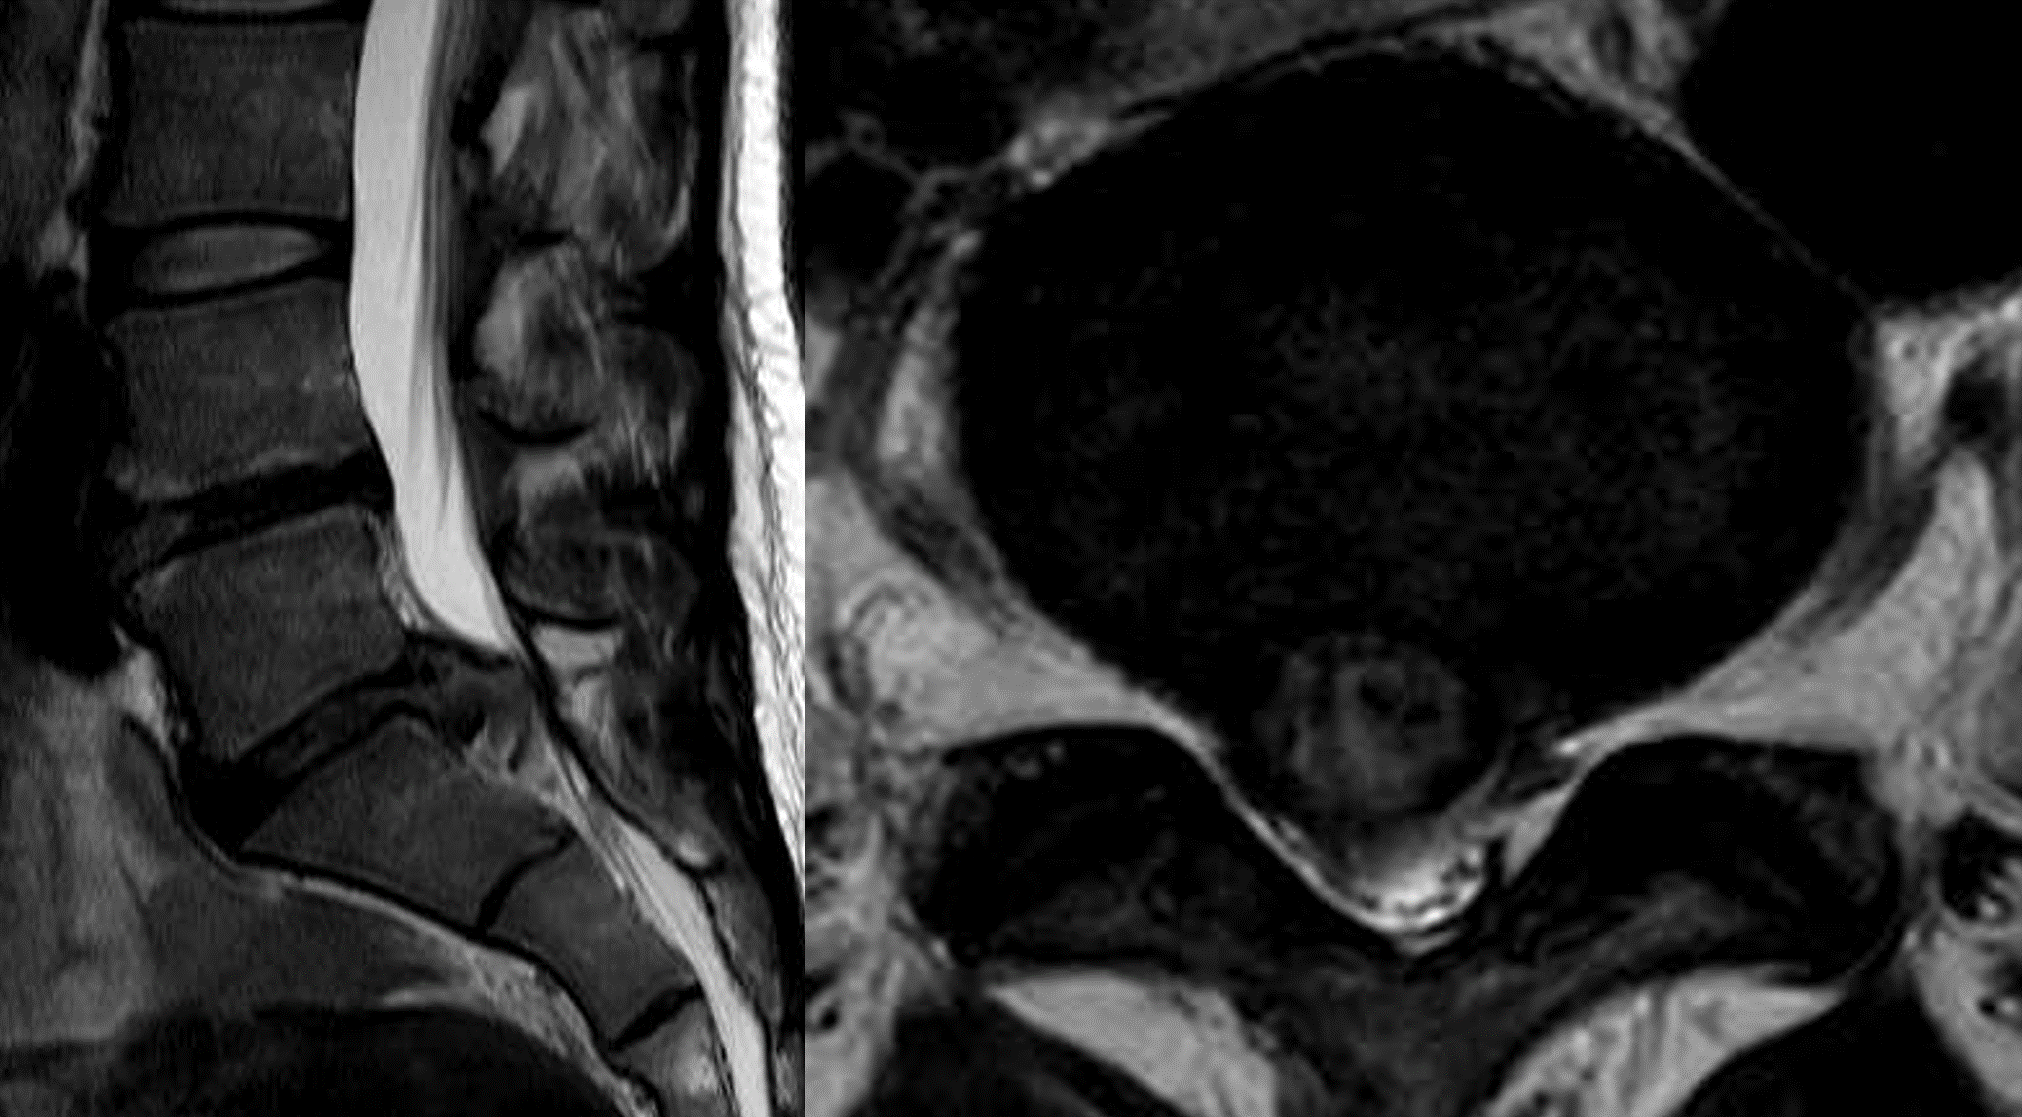

영상 검사: MRI(자기공명 영상)는 허리 디스크를 진단하기 위한 가장 중요한 검사입니다. X-ray 와 같은 단순 방사선 검사는 전방 전위증과 같은 추가적인 진단을 위해 필요할 때도 있습니다. CT (전산화 단층 촬영)의 경우 석회화 된 디스크를 감별하기 위해 촬영합니다.